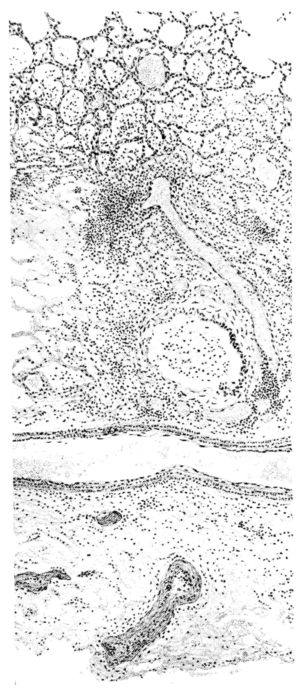

FIG. III. AUTOPSY NO. 90. DRAWING FROM A LESION OF THE TRACHEA (SOMEWHAT OLDER THAN THAT ILLUSTRATED IN FIGURE II). THE MUCOSA IS ENTIRELY LACKING. CONGESTION AND EDEMA ARE THE STRIKING FEATURES IN THE SUBMUCOSA. THE NECROTIZING PROCESS HAS EXTENDED INTO THE MUCUS GLANDS. THIS IS SHOWN IN THE LOWER PICTURE.

FIG. IV. AUTOPSY NO. 205. CONGESTION AND EDEMA OF THE SUBMUCOSA AND REGENERATION OF THE TRACHEAL EPITHELIUM.

The changes are less marked, perhaps, in the trachea than in its finer ramifications. The mucosa is constantly more or less destroyed and large areas, usually focal, are entirely devoid of their epithelial covering. This is replaced by a sparse exudate, composed largely of red blood cells, mucus, a small amount of fibrin, and nuclear fragments (Fig. II). It may dip into the submucosa for a short distance, but usually these indentures are associated with the ducts of the mucous glands into which the inflammatory reaction extends. A more striking feature than the exudate, however, is the edema and the congestion of the submucosa. The loose areolar tissue of the submucosa is spread widely apart, and throughout it distended blood vessels are very conspicuous. Occasionally such a vessel is broken and actual hemorrhage appears in the submucosa. Occasionally, too, the inflammation extends down the duct to the mucous gland itself, and here, also, aplastic inflammatory reaction is evident, inasmuch as the acini now stain intensely red with the cells undifferentiated from each other and specked here and there by broken remains of the dead nuclei (Fig. III). After the disease has continued for a short period, even at the end of five or six days, some regeneration of the epithelial lining may be seen (3) (Fig. IV). But despite this, the acute picture persists, and there goes on, side by side, an attempted repair characterized by epithelial regeneration and the same evidence of acute change. Since the lesion is essentially a superficial one, scars or contractures of any extent are not encountered in the trachea, even in examples of the disease that have ended fatally only after many weeks.[4]